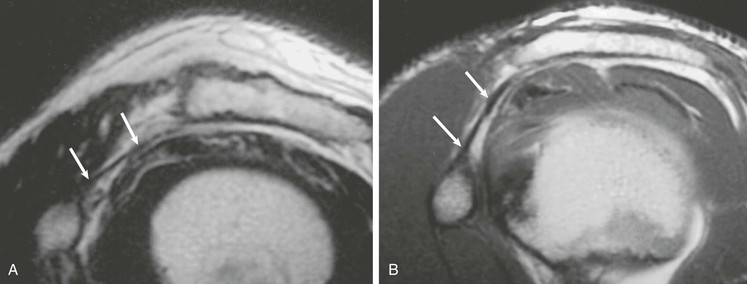

Most cuff tears originate in the supraspinatus tendon; however, large tears may extend into either the infraspinatus or subscapularis tendon. Isolated tears, although less common, occasionally occur in either the infraspinatus or subscapularis (Fig. 44-24) tendon. An isolated tear of the infraspinatus tendon is usually associated with the internal impingement syndrome (discussed further in the section on glenohumeral instability).104 An isolated tear of the subscapularis tendon may result from shoulder dislocation or in association with coracohumeral impingement112 and is best demonstrated on axial MRI as high signal traversing the tendon with retraction of the tendon away from its normal attachment site on the lesser tuberosity. An extension of the subscapularis tendon known as the transverse ligament holds the long head of the biceps tendon in the intertubercular groove, and a tear of the subscapularis tendon may result in disruption of the transverse ligament, leading to medial subluxation or dislocation of the long head of the biceps tendon.113 Axial MRI is well suited not only for evaluating the integrity of the subscapularis tendon but also for demonstrating medial subluxation of the biceps tendon out of the intertubercular groove. The biceps tendon may be displaced superficial to the subscapularis tendon, into the subscapularis tendon (Fig. 44-25) or intraarticular (Fig. 44-26).

An intramuscular cyst within the rotator cuff (Fig. 44-27, A and B) has been described as a finding associated with small full-thickness tears or partial-thickness articular-sided tears of the rotator cuff.114 Intramuscular cysts are similar to paralabral cysts of the shoulder or meniscal cysts of the knee. Fluid leaks through a defect in the cuff and tracks in a delaminating fashion along the fibers of the tendon, resulting in a fluid collection contained within either the muscle or fascia of the rotator cuff. These cysts have been reported in the supraspinatus, infraspinatus, and subscapularis muscles and appear as oval lobulated collections of low signal intensity on T1-weighted images and high signal intensity on T2-weighted images. Identification of an intramuscular cyst of the rotator cuff should prompt a thorough search for a small associated cuff tear.